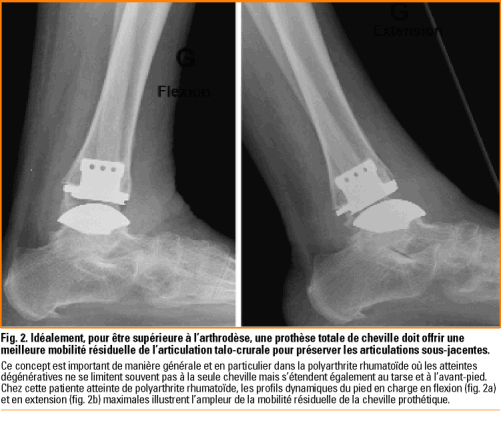

Arthrose Et Arthropathies De Cheville Prothese Ou Arthrodese Revue Medicale Suisse

Arthrose De Cheville Aujourd Hui Prothese Ou Arthrodese Orthopadie Traumatologie Universimed Medizin Im Fokus